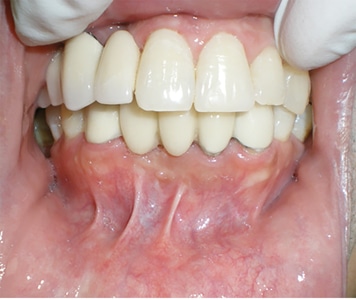

Minimally Invasive Surgical And Prosthetic Management Of A Failed Implant In The Esthetic Zone

Said-fig-18B2 alternate text for this image

Introduction Management of the peri-implant soft tissue contours is a critical component of esthetic implant therapy. In patients with high esthetic demands, minimally invasive surgical techniques and prosthetic soft tissue development are important in achieving a seamless, naturally appearing implant supported restoration. Prosthetic tissue conditioning and accurate translation of the restorative contours to the final … Read more